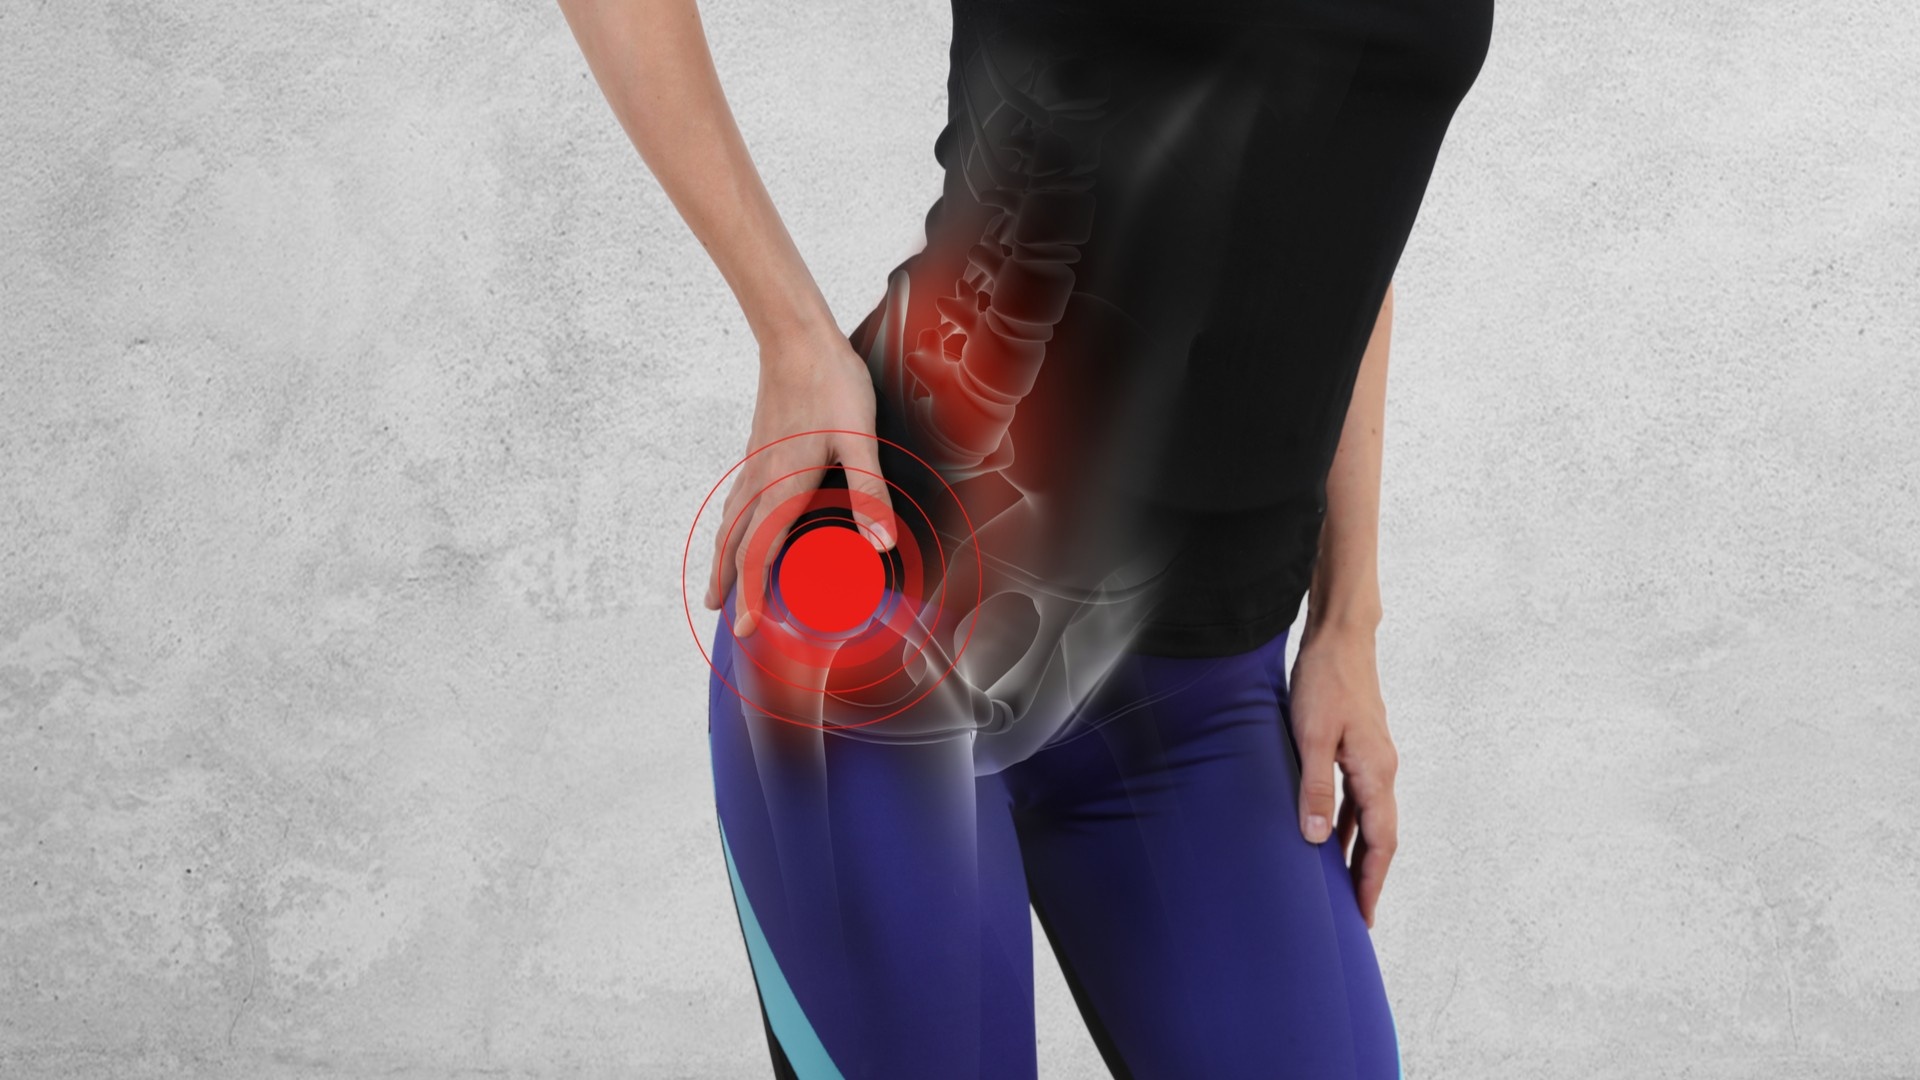

Bursitis is a painful condition that affects the small, fluid-filled sacs — called bursae.

These fluid filled sacs exist to cushion the bones, tendons and muscles near your joints.

Bursitis occurs when bursae become inflamed. The inflammation often causes pain and swelling in the area.

The most common locations for bursitis are in the:

- hip - trochanteric bursitis